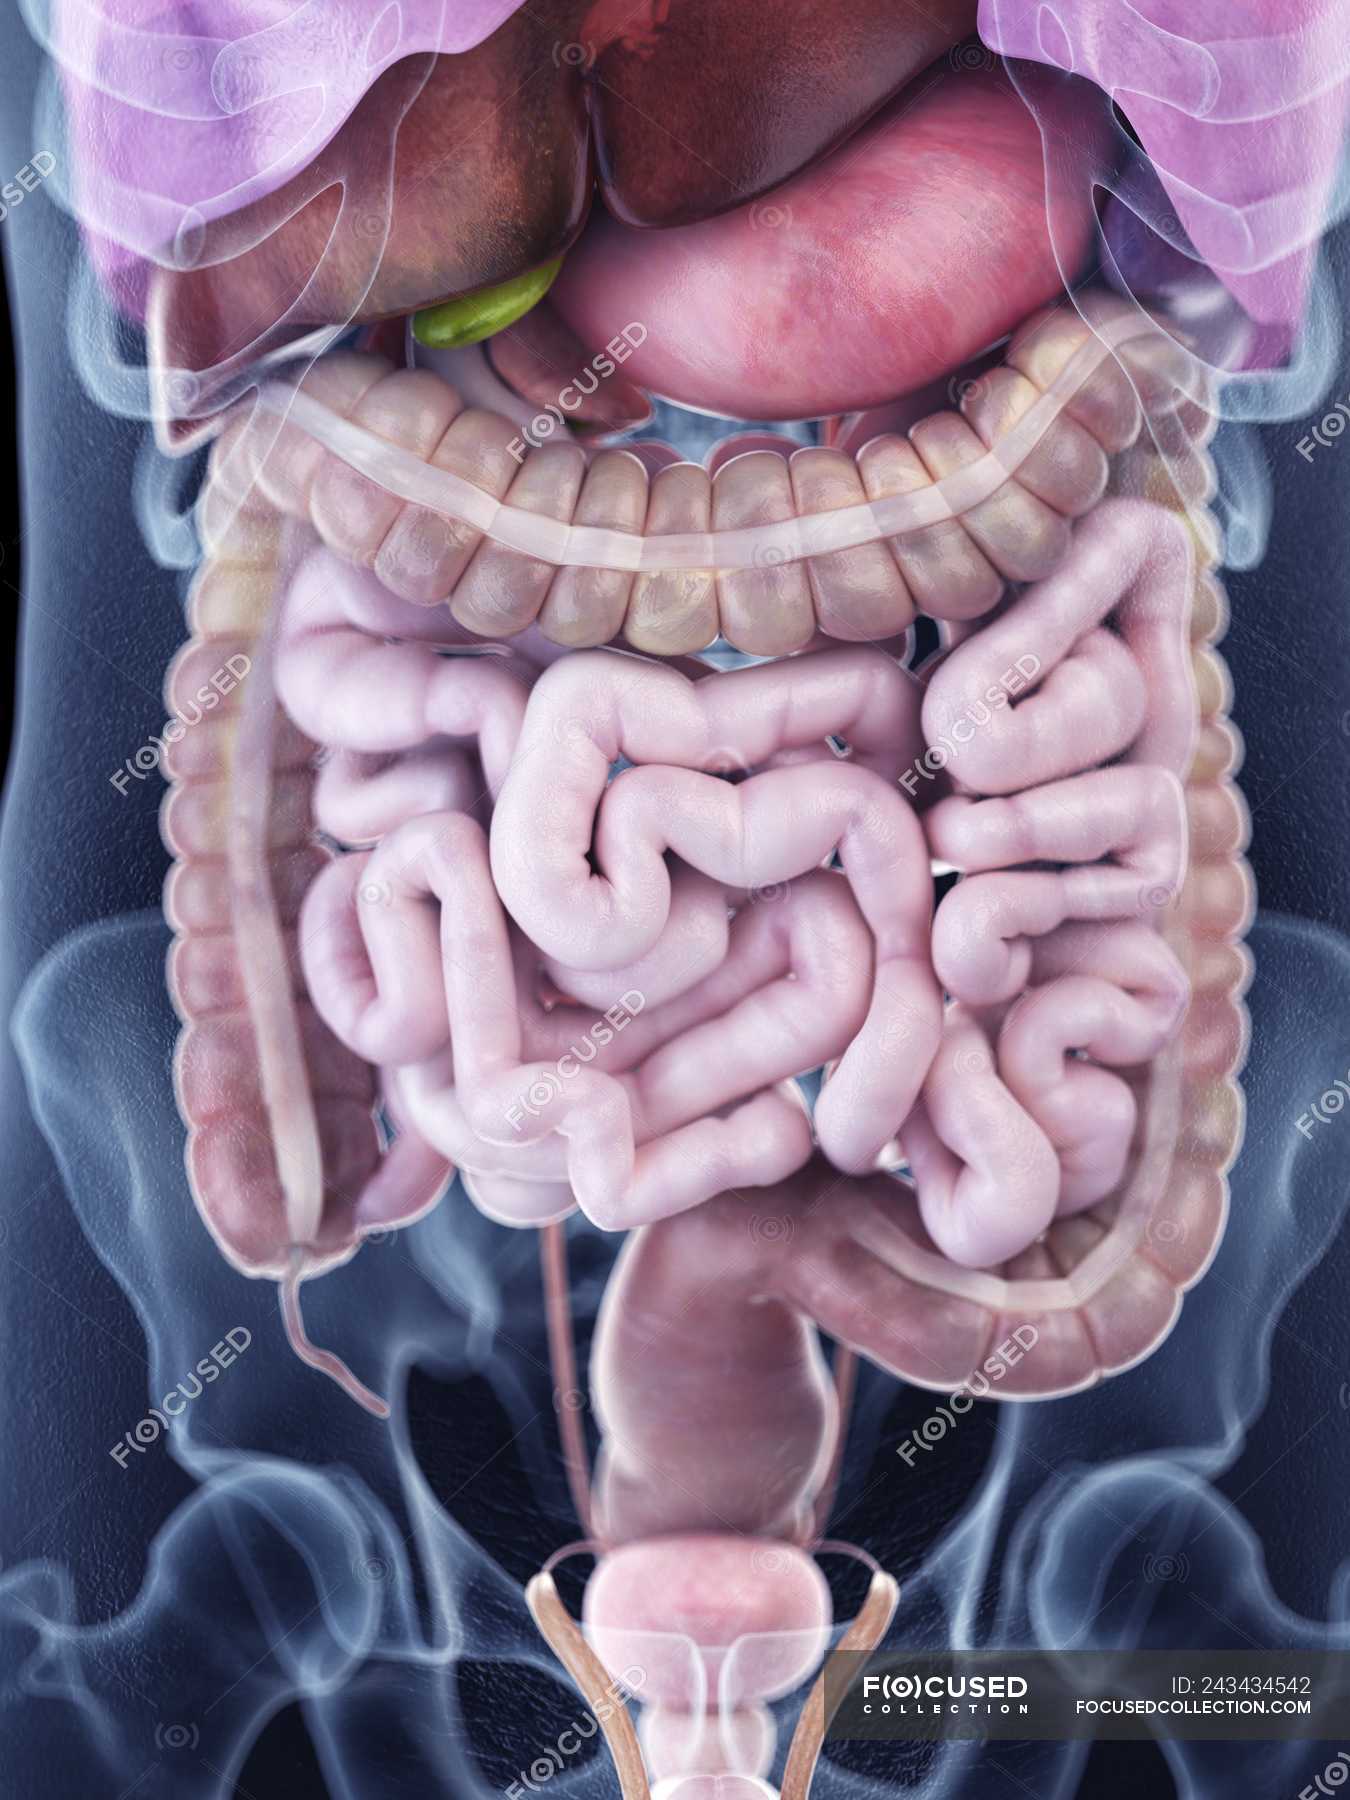

anatomychart101.storage.googleapis.comIllustration Of Human Abdominal Anatomy In Body Silhouette. — Digitally

anatomychart101.storage.googleapis.comIllustration Of Human Abdominal Anatomy In Body Silhouette. — Digitally

focusedcollection.comabdominal anatomy human anatomical

focusedcollection.comabdominal anatomy human anatomical